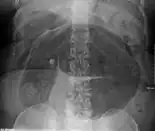

After taking a thorough history, the diagnosis of colonic volvulus is usually easily included in the differential diagnosis. Abdominal plain x-rays are commonly confirmatory for a volvulus, especially if a coffee bean sign is seen. These refer to the shape of the air-filled closed loop of colon which forms the volvulus. Should the diagnosis be in doubt, a barium enema may be used to demonstrate a "bird's beak" at the point where the segment of proximal bowel and distal bowel rotate to form the volvulus.

- Abdominal x-ray – tire-like shadow arising from right iliac fossa and passing to left

Plain X ray of a cecal volvulus